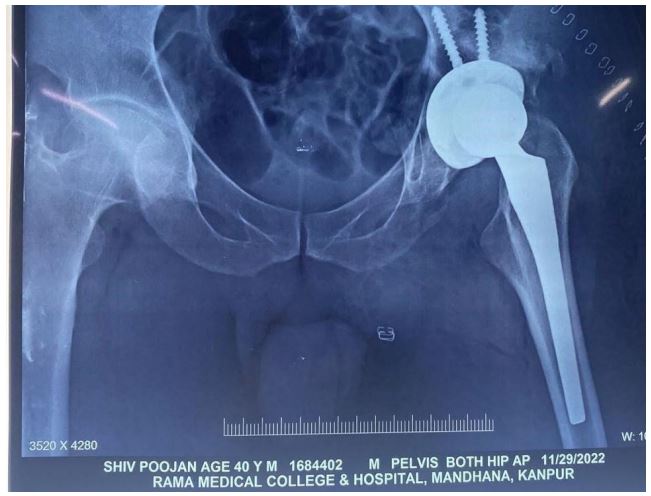

Postoperative: The patient is put on antibiotics, analgesics, antiplatelet. Patient is ambulated with the help of a walker from POD 1. Quadricep and hip abductor strengthening exercises started from POD 1. Post op x-ray done on POD 1 (Figure 2). ROM exercises started from POD 5. Suture removed on POD 14. At present 3 months of follow-up, the patient is comfortable with no pain and difficulty in walking. The patient has a good hip range of motion (Figure 6). The functional outcome is good as per Harris’s hip score.

Figure 2: Post-op x-ray of the pelvis with both hip AP view.

Figure 6: Post-op x-ray of the pelvis with both hip AP view.